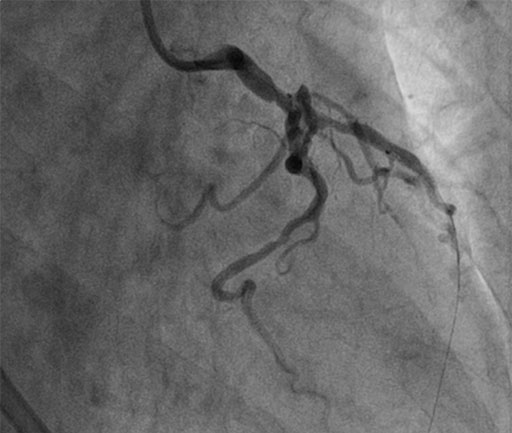

NSTEMI Intervention

• SYNERGYTM stents to proximal LAD

• Decision taken to assess 3 vessels with physiological guidance

Proceed to FFR guided PCI of 3 bystander vessels: LAD, Cx & RCA

COMET™ FFR of LAD shows non ischemic value of 0.82, no need for additional stents

FFR of LAD shows non-significant 0.82